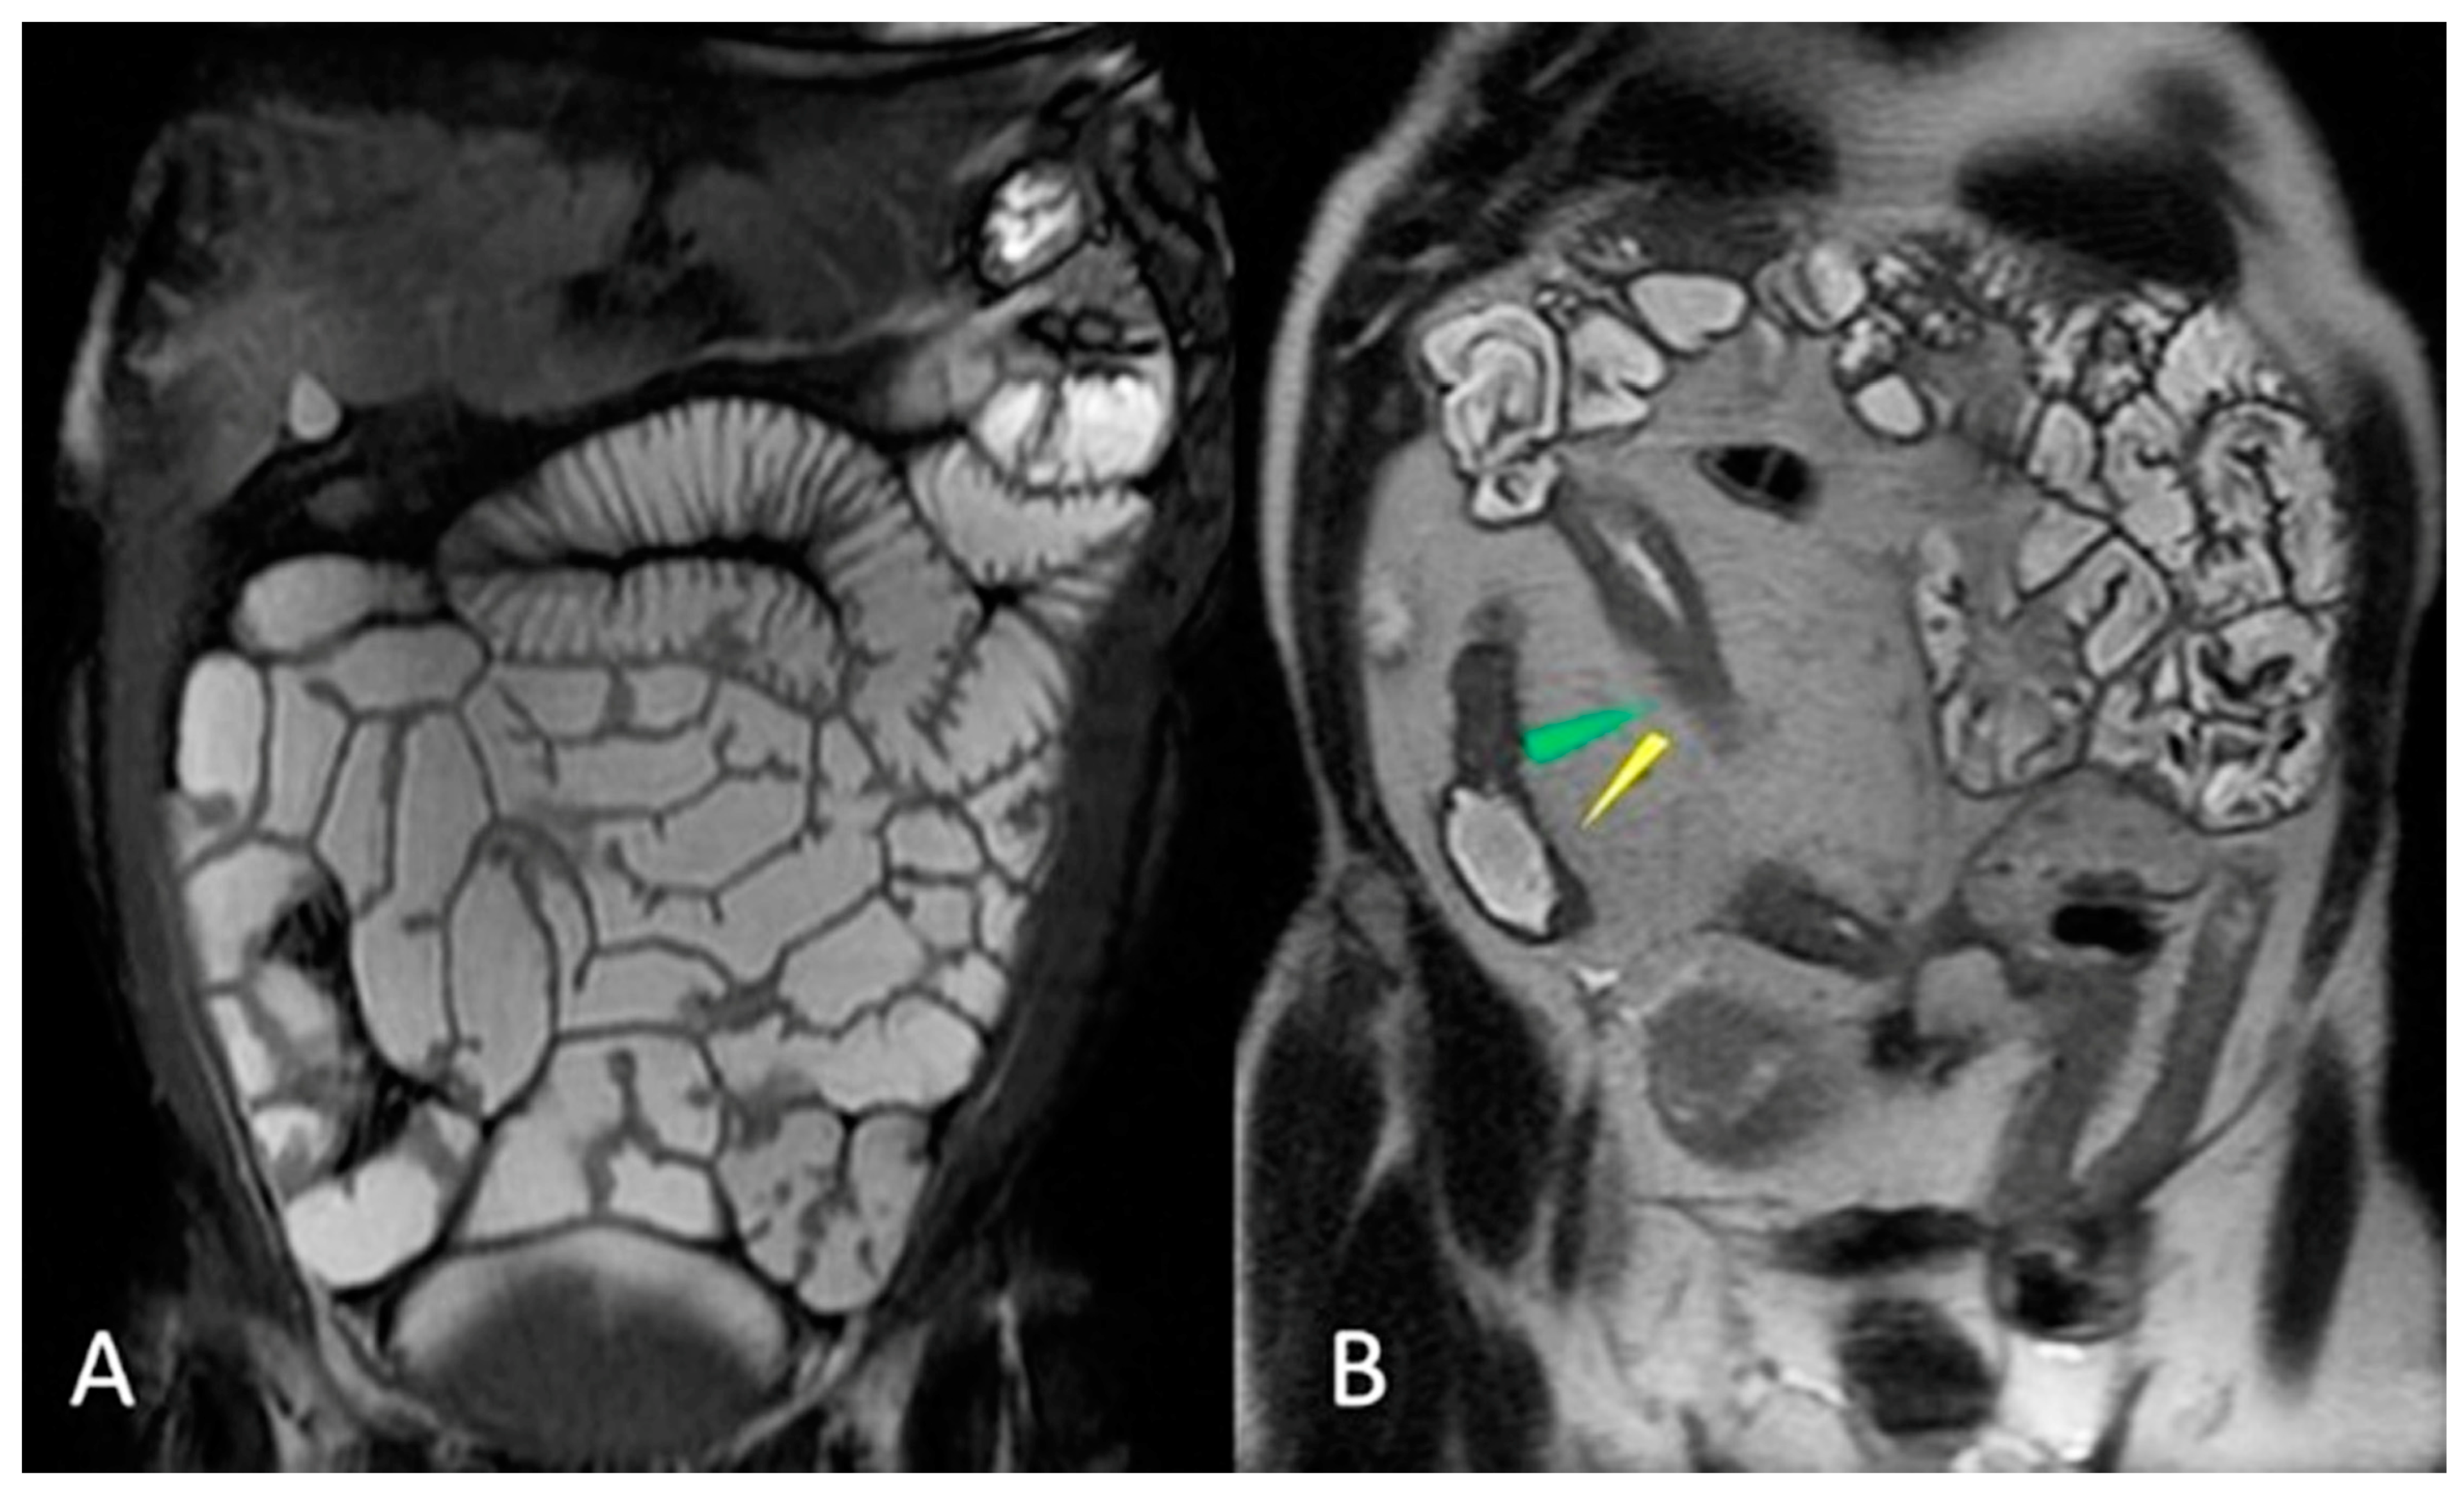

- Kavaliauskiene, G.; Ziech, M.L.; Nio, C.Y.; Stoker, J. Small bowel MRI in adult patients: Not just Crohn’s disease-a tutorial. Insights Imaging 2011, 2, 501–513. [Google Scholar] [CrossRef][Green Version]

- Sharma, D.; Nair, R.P.; Dani, T.; Shetty, P. Abdominal cocoon-A rare cause of intestinal obstruction. Int. J. Surg. Case Rep. 2013, 4, 955–957. [Google Scholar] [CrossRef]

- Cicero, G.; Blandino, A.; D’Angelo, T.; Booz, C.; Vogl, T.J.; Ascenti, G.; Mazziotti, S. Mimicking conditions of intestinal Crohn’s disease: Magnetic resonance enterography findings. Jpn. J. Radiol. 2022, 40, 19–28. [Google Scholar] [CrossRef] [PubMed]

- McLaughlin, P.D.; Maher, M.M. Nonneoplastic diseases of the small intestine: Differential diagnosis and Crohn disease. AJR Am. J. Roentgenol. 2013, 201, W174–W182. [Google Scholar] [CrossRef]